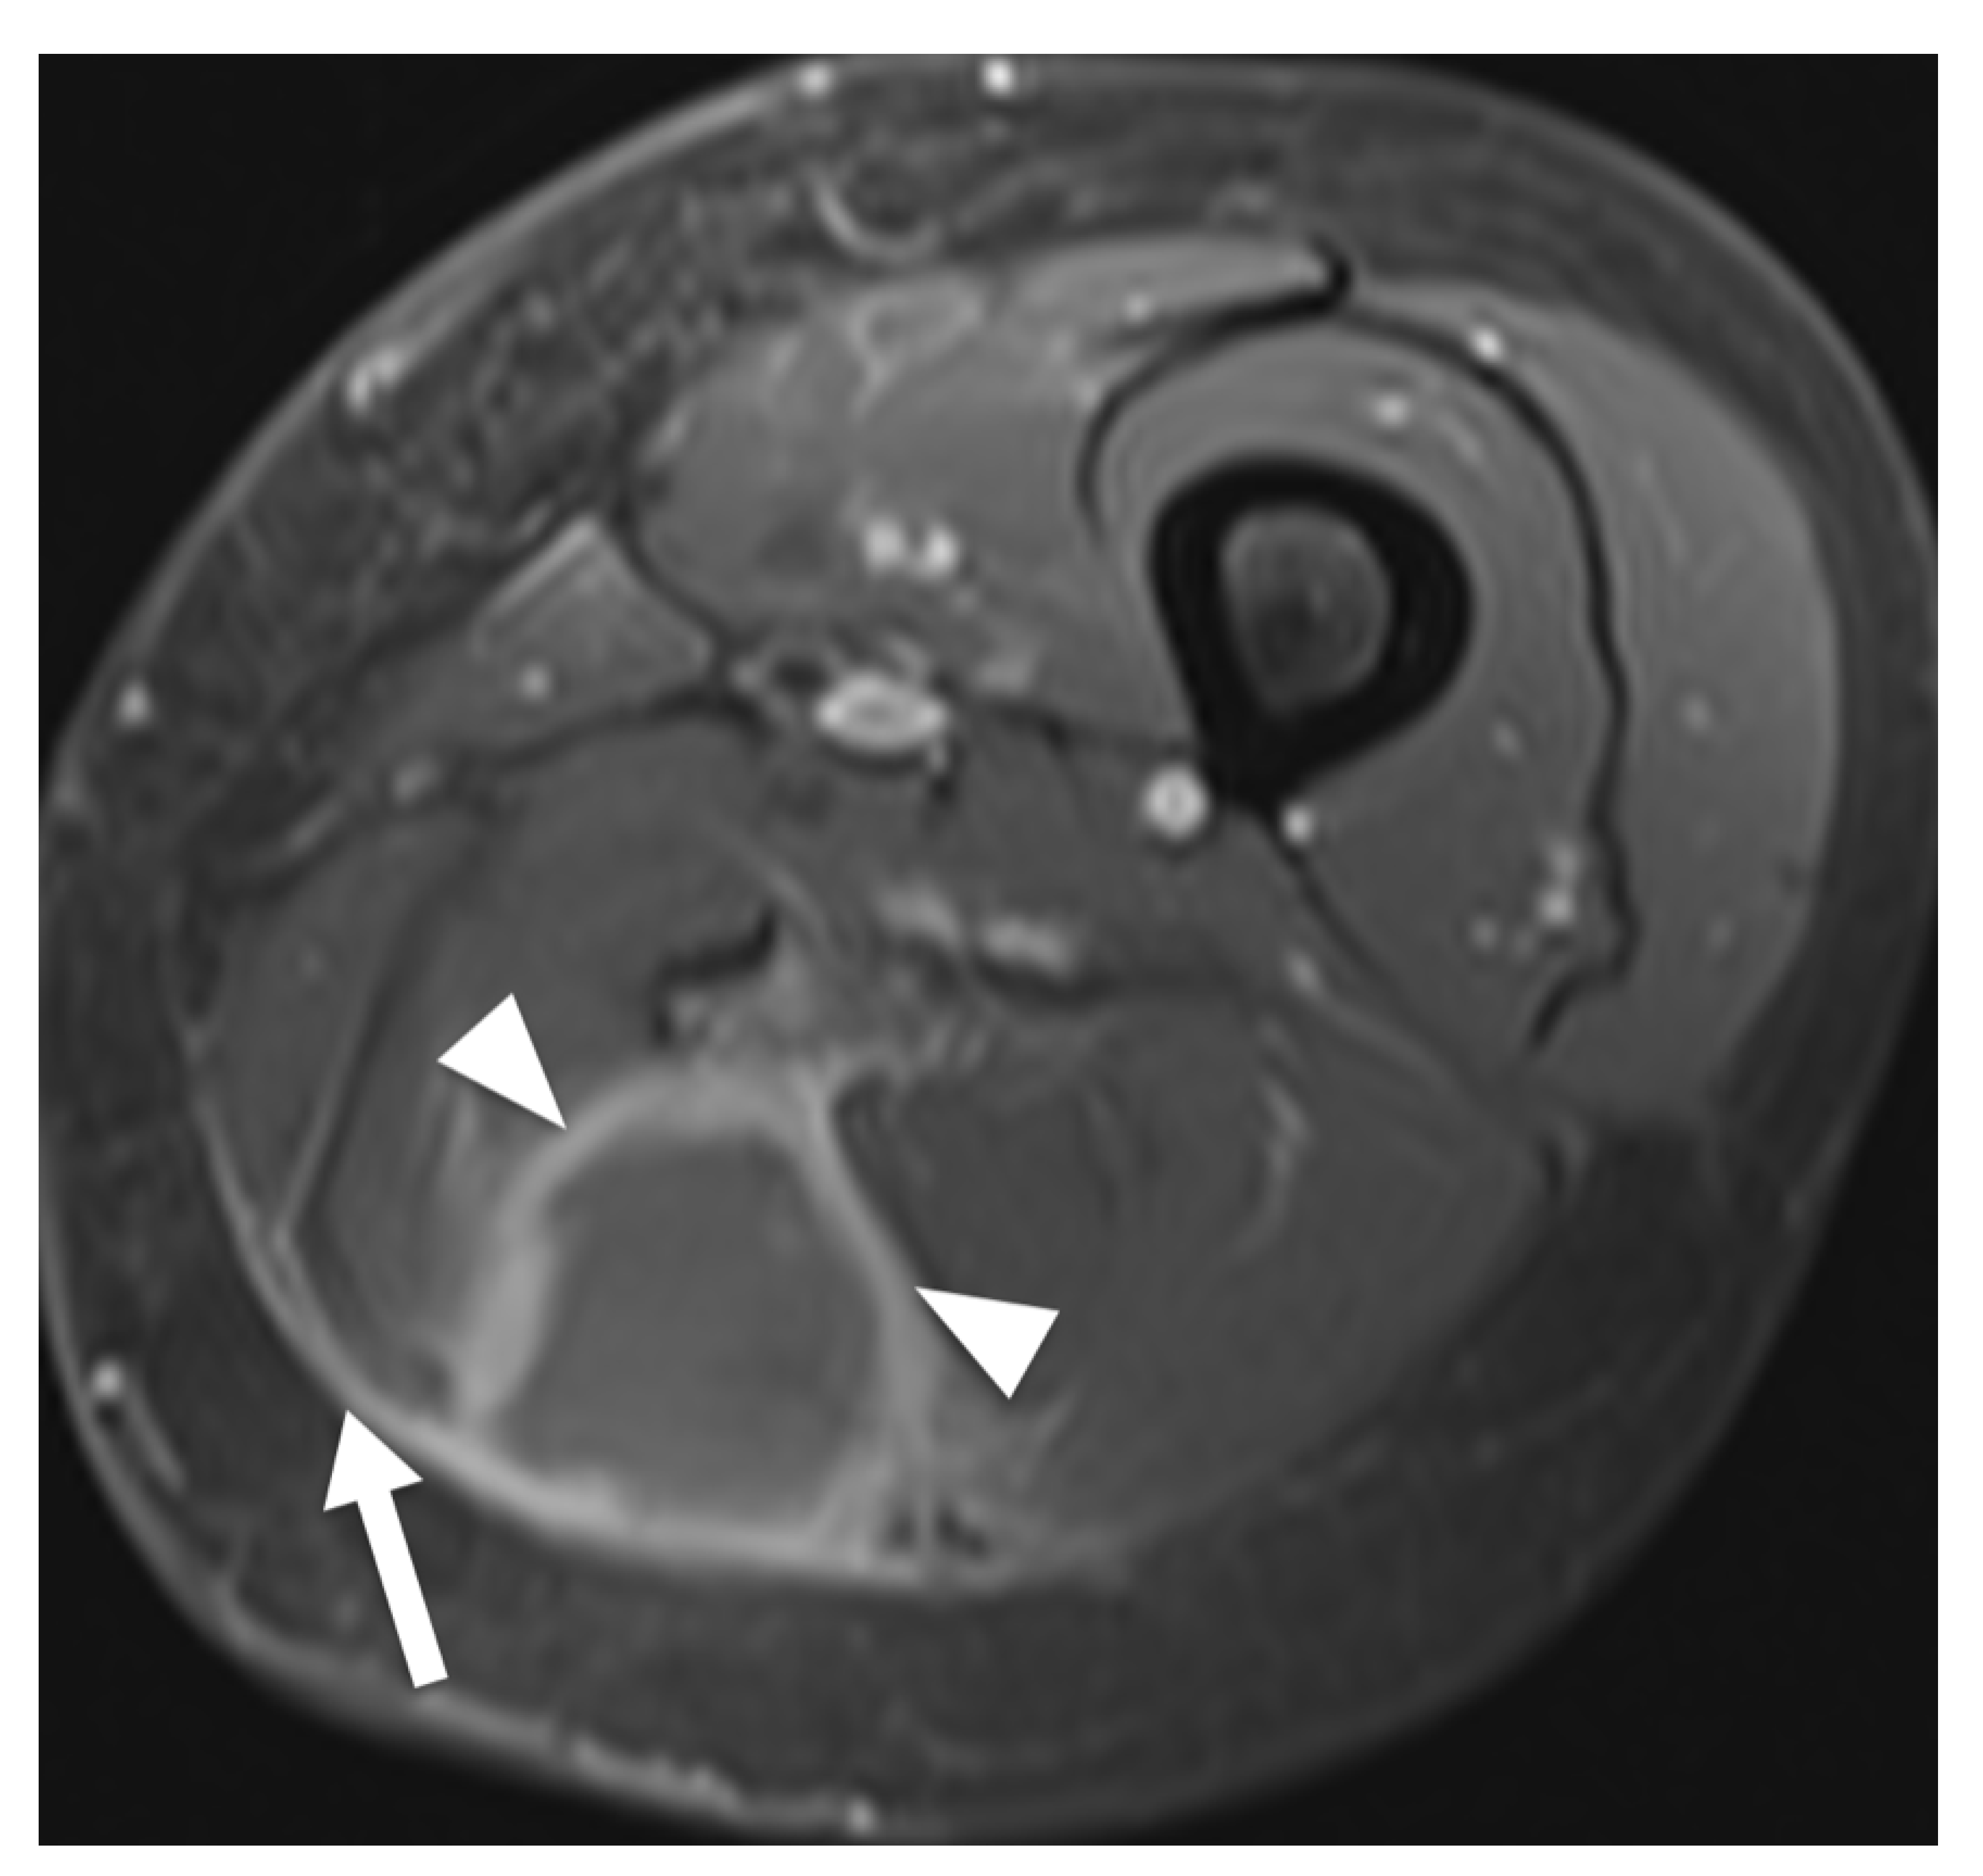

Figure 3.

MRI of a 68-year-old woman presenting with non-Hodgkin lymphoma manifestation in the thigh. Transversal contrast enhanced fat-saturated T1-weighted image shows a tumor in the posterior compartment of the thigh, revealing predominant enhancement of tumor margins (arrowheads). Moreover, signal alteration of fascia lata can be noted (arrow).

Results of extracted MRI data are displayed in Table 4. Signal intensity of lymphoma compared to muscle tissue was mostly described as isointense (53%) or slightly hyperintense (39%) in T1W images and always as hyperintense in T2W images (Figure 2). The majority of T2W images revealed either isointense (47%) or hypointense signal intensity (45%) of lymphoma compared to fat. Hyperintense signal intensity compared to muscle was reported in all PD-weighted (n = 3) and STIR (n = 18) images. In fat-suppressed T2W images, one lesion (5%) showed isointense signal intensity to muscle, nine (43%) lesions showed isointense signal intensity to fat, three (14%) lesions showed intermediate signal intensity between fat and muscle and eight (38%) lesions showed hyperintense signal intensity compared to fat. None of the included articles investigated signal intensity in T1W, PD or STIR images compared to fat. Contrast enhanced images mainly showed homogenous enhancement (62%). One study differentiated further and described the presence of thick peripheral bandlike enhancement and marginal septal enhancement (Figure 3) [30]. Furthermore, the said series reported thick irregular enhancement of deep and superficial fascia in 16 patients (84%) (Figure 2 and Figure 3) whereas isolated enhancement of deep fascia was present in one patient (5%). Two (11%) patients did not show enhancement of fascia. Margins were described as poorly defined in 22 cases (61%) and as well-defined in 14 cases (39%). Multiple affected muscles were described in 19 of 30 (63%) identified cases. The presence of multicompartmental involvement was described in 36 of 61 (59%) of patients (maximum four compartments). Additionally, behavior of ASTL was reported as “often not confined to one muscle compartment” in one study [34]. Appearance in MRI was reported as a focal mass in 22 (59%) of cases and as diffuse abnormality of signal intensity in 15 cases (41%). Hereby, results were vastly heterogenous with several studies exclusively reporting diffuse abnormalities of signal intensity [11,33,34] while Carrol et al. reported a focal tumor mass in seven out of seven patients (100%) and Chun et al. reported focal manifestation in 15 out of 20 cases (75%) [19,30]. Subcutaneous stranding was examined in 34 cases and was present in 25 (74%) of these cases (Figure 2). Moreover, skin thickening was documented in 19 of 50 (38%) investigated patients. Long segmental involvement was reported in 20 of 25 (80%) of investigated cases (Figure 2). One study reported growth along neurovascular bundles with partial or complete encasement of these structures in seven of 24 cases (29%) [18]. Furthermore, Carroll et al. reported complete encasement of adjacent neurovascular structures in two cases and partial encasement in three of five cases not limited to the subcutaneous fat [19]. (Figure 2). Signal intensity abnormalities of bone marrow were described in nine of 49 (18%) examined patients, traversing vessels were found in 20 of 24 (83%) cases and peritumoral edema was noted in 15 of 31 (48%) cases. None of the included studies described signs of encapsulation or necrosis. Only one of the included studies provided DWI data and reported low signal intensity in apparent diffusion constant (ADC) images in all 10 investigated patients presenting with soft tissue lymphoma. Thereby, computed ADC values were ranging from 0.60–0.90 mm2 s−1 (mean: 0.76 ± 0.10; median: 0.78). Additionally, fusion images of DWI and HASTE, STIR or T2W images showed high signal intensity in all evaluated cases [35].

In T2W fat-suppressed images, signal intensity was widely inconsistent. Therefore, we conclude that iso- to slightly hyperintense signal intensity in T1W sequences and hyperintense signal intensity in T2W, STIR and PDW images compared to muscle seem to be characteristic for ASTL. Homogenous contrast enhancement was reported more frequently than heterogenous enhancement and appears to be more characteristic. A previous study described enhancement of deep and superficial fascia, these findings might be related to the tendency of infiltrative, multicompartmental growth pattern of ASTL [30]. Margin descriptions of ASTL were heterogenous, ranging from poorly to well-defined. These findings are consistent with Gao et al. as ASTL margins in MR imaging appear to be nonspecific [16]. This heterogeneity might be attributed to differences in subjective MRI interpretation between studies. Multicompartmental involvement was defined as affected muscles of multiple fascial muscle compartments [11,18,30,31,32,33,34] or as involvement of various tissues [19] and was described in 36 of 61 (59%) patients (Figure 4). This feature can be useful to differentiate ASTL from soft tissue sarcoma, which are generally known to respect compartmental boundaries [15,21,34]. The presence of subcutaneous stranding was a commonly reported attribute of ASTL [13,18,30,32] and seems to be common in ASTL presentations. Explanations for these findings could be lymphomatous infiltration or reactive edema [19,38]. Furthermore, long segmental involvement, also called cone like involvement, of tumor seems to be a key feature of ASTL, being present in 20 of 25 included patients (80%), and can present inter- or intramuscularly [30,31,34]. Involvement of neurovascular structures was reported in 12 of 29 (41%) cases [18,19]. Furthermore, a previous study evaluating CT appearance of soft tissue lymphoma has found encasement of vascular structures in confluent lymphadenopathy associated with soft tissue lymphoma in six out of 13 patients (46%) [20]. These findings might be due to infiltration along lymphatic vessels accompanying the neurovascular bundle [18]. Signal intensity abnormalities of bone marrow were occasionally described and may present edema or lymphomatous infiltration [14,34,39]. They usually present without destruction of cortical bone [10] and might be due to spread of tumor through intracortical channels, first described by Hicks et al. in cases of primary osseous lymphoma [9,14]. Additionally, the presence of traversing vessels seems to be characteristic for ASTL as it was present in 20 of 24 (83%) investigated patients (Figure 4). Necrosis is generally considered as being absent in soft tissue lymphoma manifestations before treatment [8,14,37,40]; however, there are rare reports of necrosis being present in MRI of soft tissue lymphoma manifestations [18,41]. Diffusion weighted imaging seems to pose a further asset in the characterization of soft tissue lymphoma. Reported low ADC values coincide with high cellularity of lymphoma [35,42] and seem to be significantly lower than in other malignancies such as soft tissue sarcoma and lymph node metastasis [35,43,44]. This finding might be related to the tendency of soft tissue sarcoma and metastasis to express a more heterogenous, less dense cellularity than soft tissue lymphoma [44]. Moreover, DWI could be of use to monitor the treatment response, as it has been shown, that ADC values in soft tissue sarcoma increase after radiotherapy [45]. None of the included studies investigated presence of B symptoms; this may be due to reports of soft tissue lymphoma often not presenting with symptoms such as fever, weight loss and excessive night sweat [20,41]. Moreover, alteration of lactate dehydrogenase levels seems to be a possible clinical parameter of ASTL [46,47], nevertheless, none of the included studies evaluated this variable.